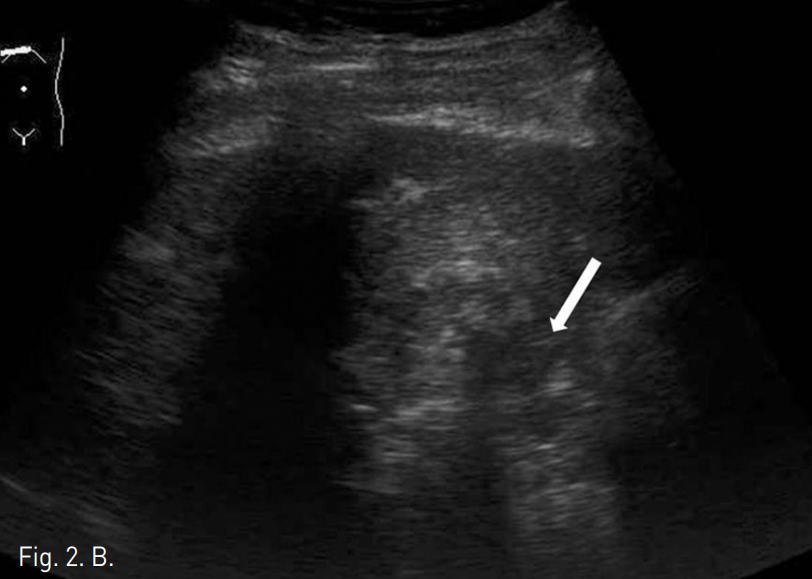

Fig. 2

A. Sonography before PEIT procedure demonstrates the adherence of the gallbladder (arrow) to the S4 HCC (arrow head).

B. Sonographic image taken after PEIT of the S4 HCC. Total 13cc absolute ethanol has been injected at both lateral and inferior aspect of the mass with the remnant portion measured as 1.5x1.8cm (arrow).

C. Sonography during the RFA ablation of the remnant tumor. RFA probe with 2cm ablation tip was used.